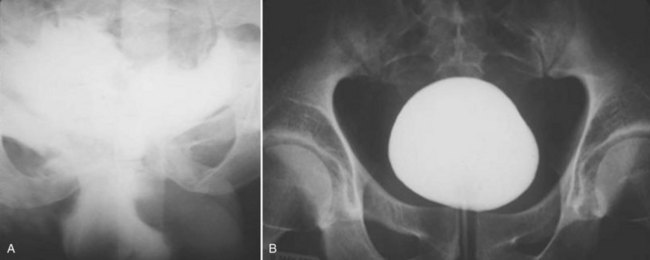

Because CT is now routinely used to assess trauma patients, concomitant CT cystography is now frequently selected as a more efficient means to assess the bladder. CT cystography is as accurate and reliable as plain film cystography to evaluate suspected bladder injury (Fig. 88–10), as long as the bladder is filled in retrograde fashion with contrast material diluted to 2% to 4% (6 : 1 with saline) to a volume of 350 mL (Peng et al, 1999; Hsieh et al, 2002). Drainage films are not required after CT cystography because the retrovesical space can be well visualized with axial images (Morey and Carroll, 1997). Dilution of the contrast material is mandatory because undiluted contrast material is so dense that the CT quality is compromised by scatter artifact. Clamping the urethral catheter in an attempt to allow antegrade distention of the bladder by intravenous contrast medium is inadequate for diagnosis of bladder rupture—retrograde filling is required. Conventional abdominal CT of the trauma patient may show findings suggestive of bladder injury but is not considered to be adequate for bladder evaluation without retrograde contrast distention (Mee et al, 1987; Udekwu et al, 1996; Hsieh et al, 2002).

The usual treatment of uncomplicated extraperitoneal bladder ruptures, when conditions are ideal, is conservative management with urethral catheter drainage alone (Fig. 88–11). A large-bore (22 Fr) Foley catheter should be used to promote adequate drainage—if output is poor, fluoroscopic cystography should be considered to ensure proper catheter placement. Cystography is necessary to verify complete healing before catheter removal 14 days after injury; occasionally, extravasation may persist for several additional weeks but will resolve with continuation of urethral catheter drainage, after which radiographic confirmation of healing is essential. Bone spicules within the bladder wall (Fig. 88–12 on the Expert Consult website)

Figure 88–11 A, Dense flame-shaped pattern of contrast extravasation in pelvis due to extraperitoneal bladder rupture. B, Repeated cystogram in same patient after 2 weeks of catheter drainage shows completely healed bladder.